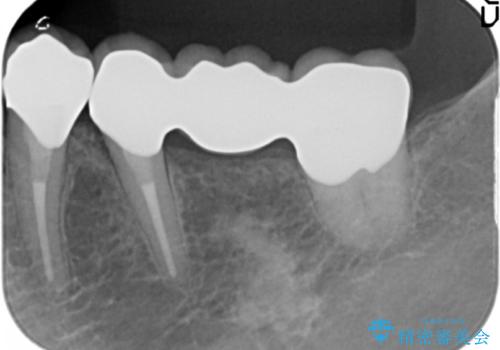

- 46万円(仮歯・ファイバーコア・ジルコニアクラウン×4)費用は治療当時の料金となります

口腔内に金属色でないブリッジが入り、口を開けて笑うことがはずかしくなくなっと喜んでいただきました。